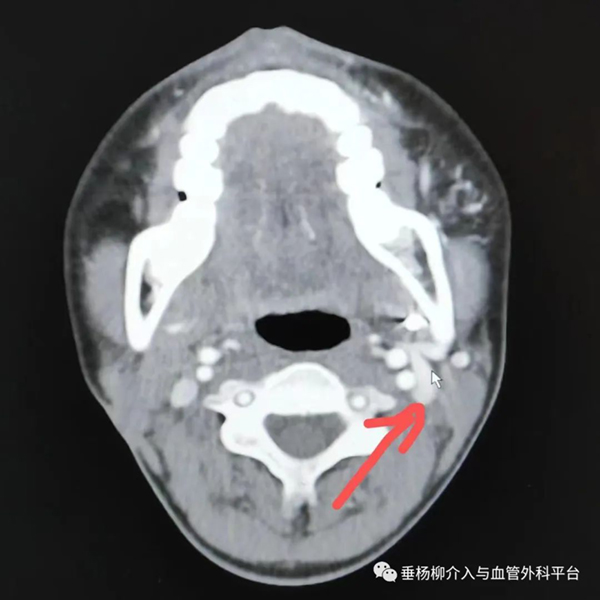

2.增强CT是可疑颌骨中心性血管瘤病变的首要辅助检查手段,颌骨骨髓腔内动脉性强化的血管团块是颌骨中心性血管瘤的特征性表现。此外,在颌骨动静脉畸形患者的头颈部增强CT中,可观察到患侧颈外静脉较对侧增粗的现象,提示病变侧出现静脉系统压力增高的血流动力学状态,可反映病变区动静脉瘘瘘口情况。

左下颌骨中心性血管瘤患者的头颈部增强CT显示颈外静脉增粗(箭头)